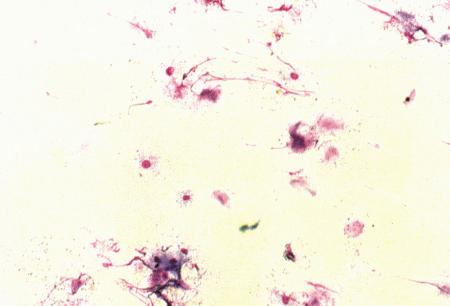

Фиг. 7.4.

(а, b) мазки секрета простаты при остром простатите у кобеля. Присутствует большое количество нейтрофилов, бактерий и разрушенных клеток.